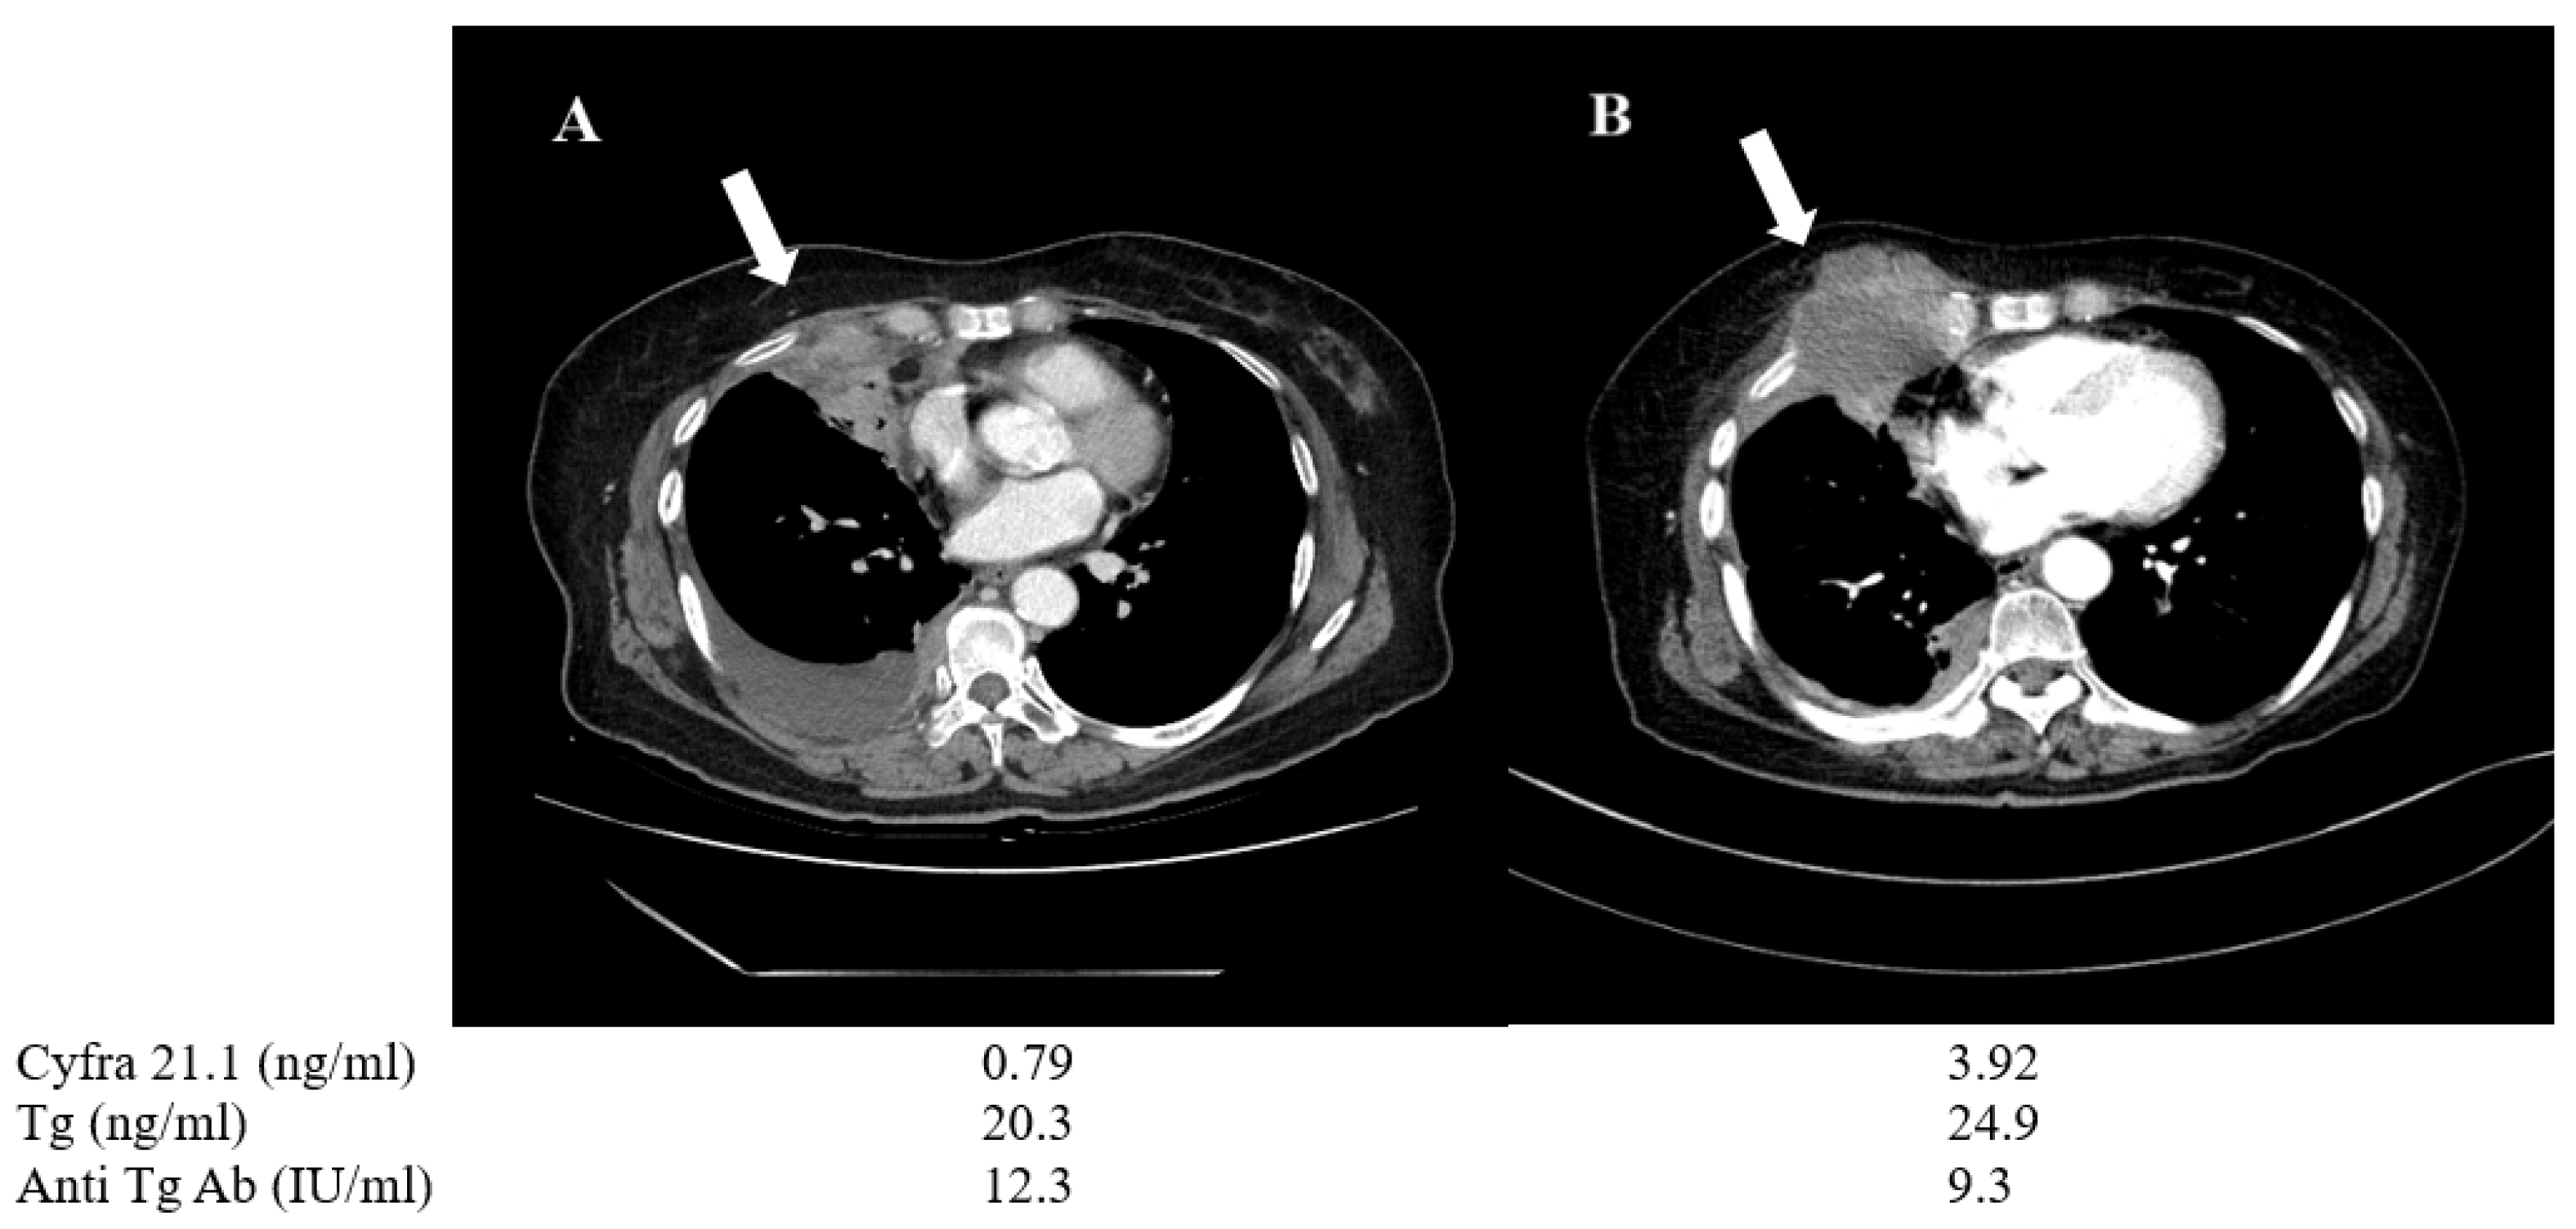

A 70-year-old female patient (No. 6) was diagnosed with pleural wall and pulmonary metastasis derived from PTC during the initial presentation. She underwent radioiodine therapy with 150 mCi, but the metastatic lesions were refractory to treatment. The patient was treated with TKIs, including sorafenib and lenvatinib, sequentially for almost one year. During the treatment, her Cyfra 21.1 level increased from 0.79 to 3.92 ng/mL, while serum Tg level changed only from 20.3 to 24.9 ng/mL. Follow-up chest CT showed progressive disease involving chest wall tumor mass and the tissue biopsy confirmed anaplastic change from primary PTC, suggesting de-differentiation (Figure 6).

Figure 6.

Changes in chest CT images and serum biomarkers of a 70-year-old PTC female (patient No. 6) before (A) and after one year of TKI treatment (B). During the time interval, the tumor progressed and changed to anaplastic feature (arrow).